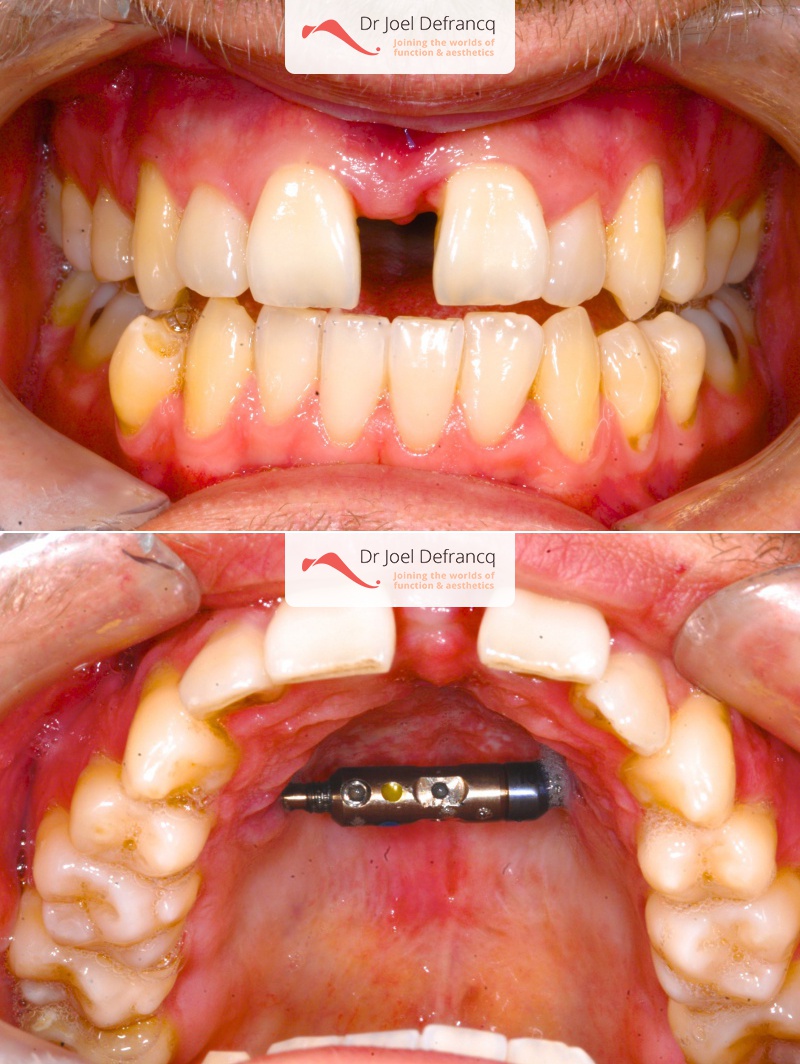

Natan: Kaakchirurgie voor en na. Te nauwe bovenkaak

Diagnose van het gezicht

- Te kleine bovenkaak

Dentale diagnose

- Klasse III

- Randbeet

Kaakchirurgie

- Verlenging bovenkaak (Le Fort I)

- Verbreden bovenkaak (Smile distractor)